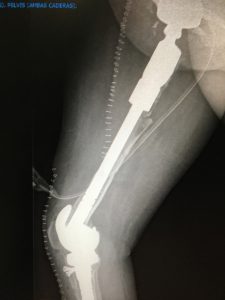

Prótesis tumorales (megaprótesis)

Diseñadas para sustituir grandes segmentos óseos resecados por tumores, generalmente en extremidades largas como fémur, húmero o tibia. Son altamente personalizadas.